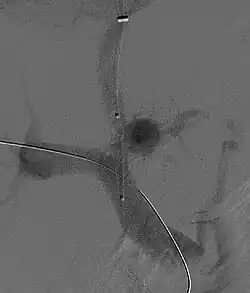

![]() Fluoroscopic image of TIPS in progress. A catheter has been passed into the hepatic vein and after needle puncture, a guidewire was passed into a portal vein branch. The tract was dilated with a balloon, and contrast injected. A self-expandable metallic stent has yet to be placed over the wire. | |

Once the catheter is in the hepatic vein, a wedge pressure is obtained to calculate the pressure gradient in the liver. Following this, carbon dioxide is injected to locate the portal vein. Then, a special needle known as a Colapinto or Rösch-Uchida is advanced through the liver parenchyma to connect the hepatic vein to the large portal vein, near the center of the liver.[13] The channel for the shunt is next created by inflating an angioplasty balloon within the liver along the tract created by the needle. The shunt is completed by placing a special mesh tube known as a stent or endograft to maintain the tract between the higher-pressure portal vein and the lower-pressure hepatic vein. After the procedure, fluoroscopic images are made to show placement. Pressure in the portal vein and inferior vena cava are often measured as the dynamic changes in the portal pressure system can help predict mortality after TIPS.[11][14]